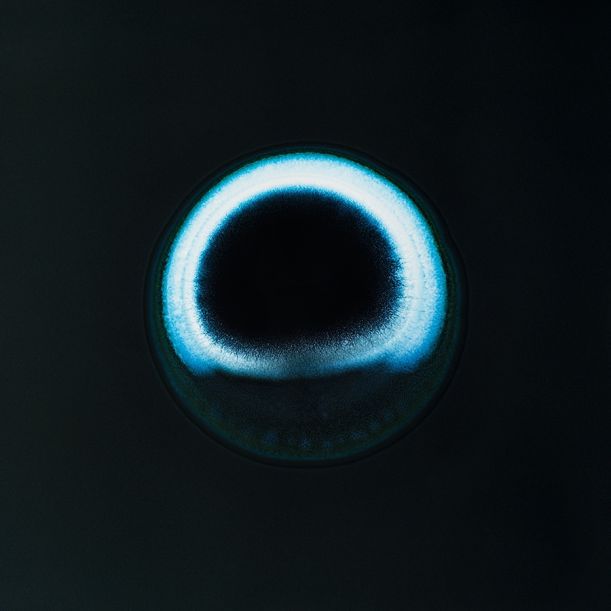

5. MDMA

Čistá krystalická extáze – mnohem silnější než barevné pilulky. Budete se sice cítit skvěle, i když chvílemi až tak, že to půjde těžko ustát, ale připravit se můžete i na sucho v ústech, skřípání zubů, svírání čelistí, nevolnost, pocení, cukání svalů i očí, eventuálně křeče, dehydrataci a následnou depku.